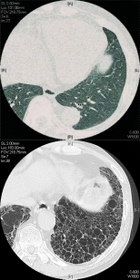

高分解能コンピューター断層撮影(HRCT)で撮影した正常な肺(上)と特発性肺線維症患者の肺(下)。患者の肺は線維化が進み、蜂の巣のような形に変化している(望月吉郎医師提供)